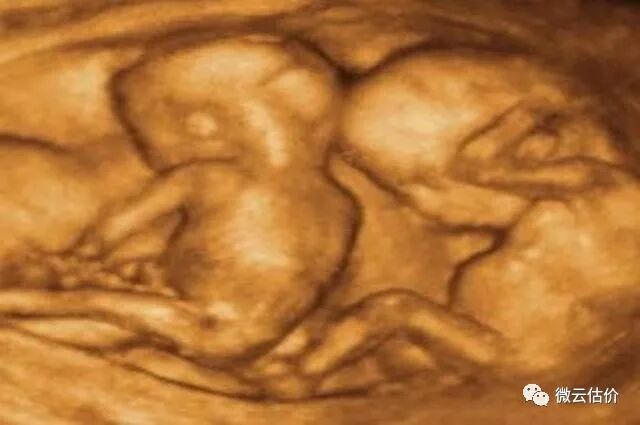

后来,医生检查完后,终于真相大白。没错,小熊是如假包换的处女,孩子也是如假包换的孩子,只不过确实不是小熊的孩子。那怎么会,又怎么可能出现在小熊的肚子里呢?在场的医生都无法解释,但是妈妈的一件往事引起了大家的注意:事情还要从小熊的妈妈说起,原来小熊的妈妈当初怀上的是双胞胎!也就是说,小熊应该有一个姐姐或者妹妹的,一些江湖通灵人则认为,小熊很可能把她的“姐姐”或者“妹妹”给“吃掉了”。

其实,当年小熊妈妈没有做太多产检,所以根本不知道自己怀上的双胞胎,更不知道的是,发生了双胞胎输血综合征,简单的来说就是,这是一种特殊的双胎妊娠并发症,小熊和另一个胎儿共用的是同一个胎盘,但是两个人之间血管吻合出现了问题,一个人的深部动脉和另一个的静脉发生了吻合,所以有一个人的血液会源源不断的被吸收到另一方的身体内,所以后来的事情,大家也就知道了......小熊“生下”了自己的“姐姐(妹妹)”!这也才会出现明明是如假包换的处女,却未婚先孕的天方夜谭了。